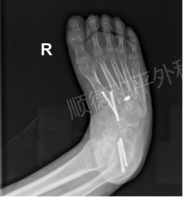

华女士自幼患有右足内翻畸形(马蹄足),足踝僵硬内翻、行走疼痛伴随她度过48年。50岁那年,她选择来到顺德和平外科医院寻求治疗。经详细查体和影像评估,骨四区团队决定实施矫形手术:通过马蹄内翻畸形松解矫形、跟腱延长、肌腱转位、多关节截骨复位融合等十余项操作,一次性解决畸形、疼痛与功能障碍。

术后摄片显示关节对合良好,内固定稳定;一个月复查时伤口愈合,肿胀消退;三个月随访时,华女士已逐渐摆脱助行器,向着行走自如、步态稳健走去,笑容自信洋溢。48年的畸形束缚被彻底打破,她的生活从此步入了新篇章。